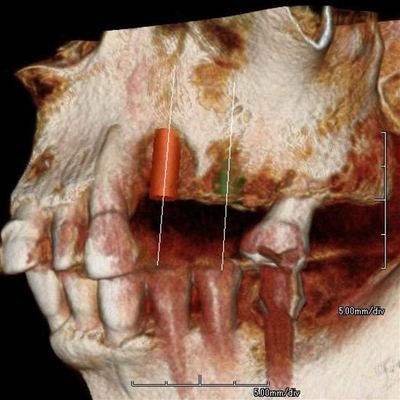

左上臼歯部のCT画像です。

2本の埋入計画を立てますが第一小臼歯部分に骨欠損があります。